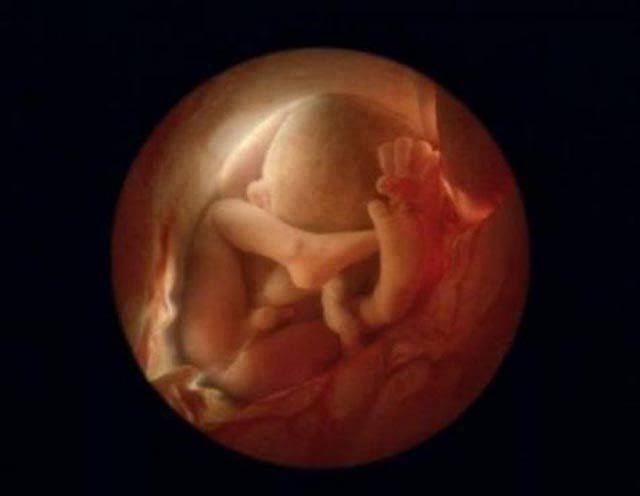

Dopo la ventesima settimana inizia ad apparire una leggera peluria. Al sesto mese il bambino inizia a muoversi, girarsi e a mettersi nella posizione giusta per venire al mondo.

Queste immagini straordinarie sono state raccolte da Nilsson in un libro chiamato, appunto, ‘Vita’. Nella raccolta ci sono anche sequenze di immagini che ricostruiscono le origini della vita umana, dei cromosomi, del DNA, dello sviluppo dei vari organi, dei sensi e dei tessuti.